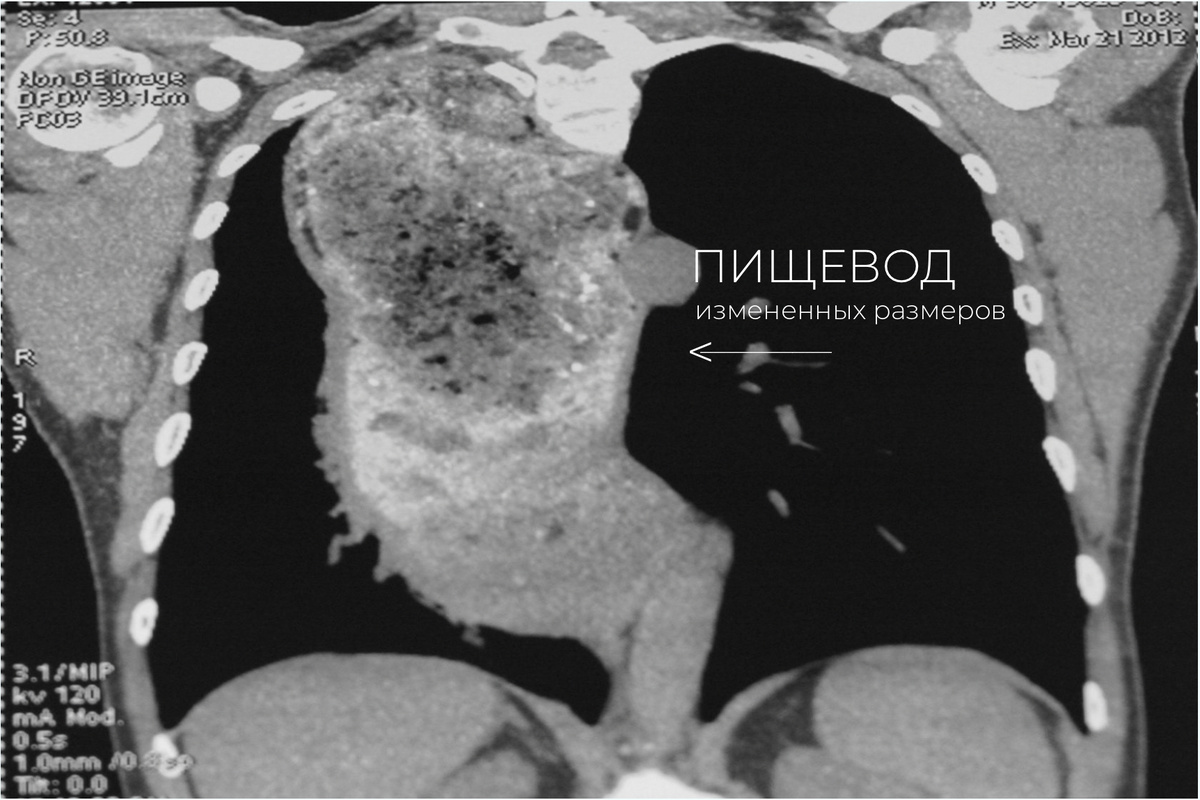

Мультиспиральная компьютерная томография (МСКТ) пациентки с ахалазией кардии IV стадии

У нашей пациентки пищевод был растянут до 15 см. Он образовывал складки, а за счет застоя пищи и хронического воспаления в нем образовались маленькие дырочки (свищи) в окружающие ткани грудной полости.

Пища из него забрасывается в дыхательные пути и вызывает хроническое воспаление легких. У нашей пациентки пищевод был растянут до 15 см. Он образовывал складки, а за счет застоя пищи и хронического воспаления в нем образовались маленькие дырочки (свищи) в окружающие ткани грудной полости.